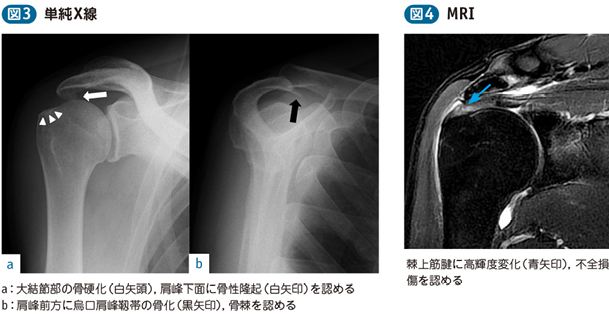

大結節骨折 画像診断key Book トレーニング 造影剤と画像診断情報サイト Bayer Radiology

大結節骨折 画像診断key Book トレーニング 造影剤と画像診断情報サイト Bayer Radiology

肩関節インピンジメント症候群 電子コンテンツ 日本医事新報社

腱板損傷 腱板断裂 のリハビリから手術まで 医療法人社団景翠会 金沢病院グループ